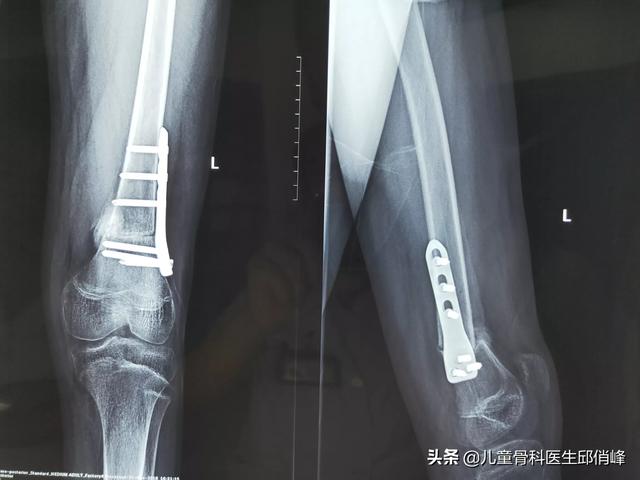

从上往下,股骨分股骨头,股骨颈,股骨大小粗隆,中间比较直的这段叫做股骨干。再往下有个斜坡的地方叫股骨髁上,下面两个鼓起来的地方叫做股骨内外髁。

我们说的股骨中段粉碎性骨折,指的是整个股骨中间占1/3左右范围内的骨折。

严格来说,股骨粉碎性骨折,可以包涵股骨头到股骨髁整个股骨的多处骨折,范围要大得多。

不过我们的骨科医生,为了交流方便,经常把股骨中段骨折直接说成股骨骨折。涉及上下端的骨折,我们都有特殊的名字,例如,股骨髁间骨折,髁上骨折,股骨颈骨折,股骨粗隆骨折过转子间骨折,粗隆下骨折等等!